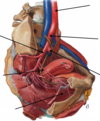

vrai ou faux

chaque pompe (coeur) est doté d’une oreillete et un ventricule

vrai

Le coeur propulse le sang appauvri en O2 aux poumons

Le cœur droit propulse le sang appauvri en O2 aux poumons

Le cœur propulse le sang riche en O2 dans l’ensemble de l’organisme

Le cœur gauche propulse le sang riche en O2 dans l’ensemble de l’organisme

Le transporte le sang provenant du cœur droit

Le tronc pulmonaire transporte le sang provenant du cœur droit

L’ transporte le sang provenant du

cœur gauche

L’aorte transporte le sang provenant du

cœur gauche

Qu’est ce qui se jettent dans le coeur droit?

Les veines caves supérieure et inférieure (VCS et VCI) se jettent dans le cœur droit;

Les débouchent dans le cœur gauche

Les veines pulmonaires débouchent dans le cœur gauche

Ou sont localisées les valves auriculoventriculaires droite (tricuspide) et gauche (bicuspide ou mitrale) ?

Les valves auriculoventriculaires droite (tricuspide) et gauche (bicuspide ou mitrale) sont localisées à l’entrée du ventricule.

À quoi servent les valves auriculoventriculaires droite (tricuspide) et gauche (bicuspide ou mitrale) ?

empeche le retour du sang des ventricules vers les oreillette